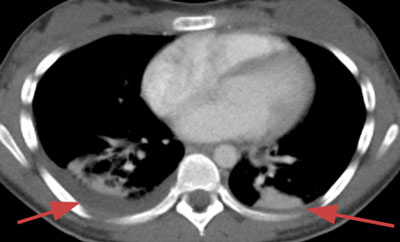

Initialt var diagnosen oklar, men på grund av misstanke om nekrotiserande fasciit i halsområdet gavs trippelbehandling med meropenem, klindamycin, och metronidazol. Tanken på Lemierres syndrom väcktes då datortomografi (DT) av hals och torax visade begynnande trombotisering av vena jugularis interna på vänster sida och embolisering till lungorna (Figur 1 och 2). Diagnosen bekräftades då blododlingar visade växt av Fusobacterium necrophorum i två av fyra flaskor. I svalget växte streptokocker grupp C eller G (slutlig speciesbestämning saknades). Anaerob odling utfördes inte då specifik frågeställning om F necro­phorum inte angavs. Serologin av Epstein–Barr-virus (EBV) visade på genomgången primärinfektion. Dalteparin gavs initialt men sattes ut då senare DT-undersökning inte visade progress av trombosen i jugularis­venen, men däremot tillkomst av pleuravätska (Figur 3). Flickan vårdades på barnavdelning från dygn sex. Där gavs behandling med bensylpenicillin och metronidazol intravenöst. Hon skrevs ut till hemmet med peroral klindamycinbehandling. DT-kontroll (hals, torax) i samband med återbesök en månad senare visade normala förhållanden, varför klindamycin avslutades. Hon mår nu bra.

Figur 1. A: axiala snitt från DT-hals med kontrastmedelsinjektion visar en liten väggfast septisk trombos (inringad) anteriort i vänster vena jugularis interna.

Figur 1. B: sned, sagittalt rekonstruerad DT-bild visar väggfast septisk trombos (inringad) och förstorade cervikala lymfkörtlar.